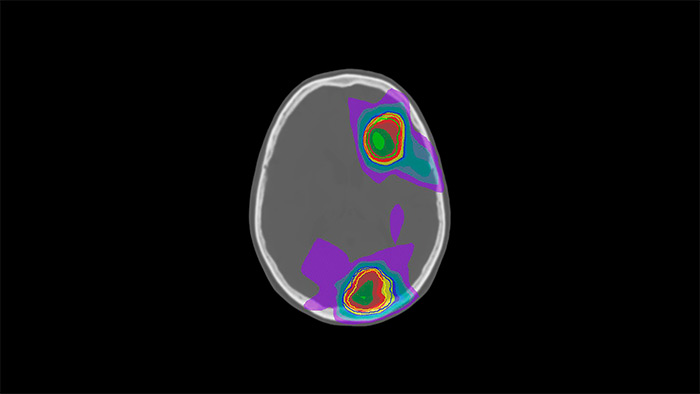

MRCAT Brain

MRCAT Pelvis

MRCAT Prostate + Auto-Contouring

MR-linac simulation package